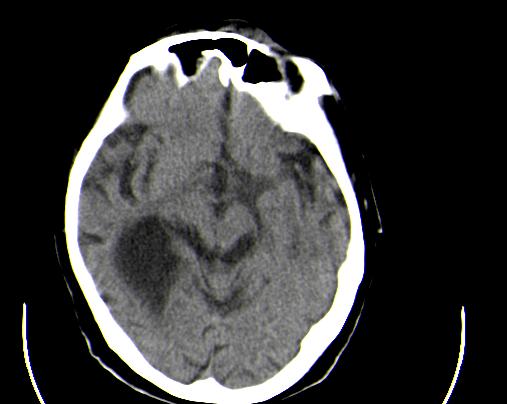

定位:右侧脑室三角区扩大,呈球形,侧脑室颞角扩大。

考虑:1、右侧侧脑室三角区室管膜囊肿?皮样囊肿?

2、脑萎缩。

神经上皮囊肿为先天性疾病,可发生在脉络丛、脑室内、脉络膜裂,少数位于脑质内,侧脑室三角区最为常见。按发生部位和囊壁的细胞学类型可有不同的命名。位于脉络丛者为脉络丛囊肿,常两侧同时发生。脑室内者为室管膜囊肿,多位于侧脑室三角区。脉络膜裂囊肿可以是神经上皮囊肿,也可以是蛛网膜囊肿。 囊肿呈脑脊液样低密度,边界清楚整齐。患者多无症状,有症状者多为头痛、癫痫发作。囊壁很薄,ct一般不能显示,囊壁无钙化。囊肿可有占位效应,表现为相应部位的脑室或脉络膜裂较对侧扩大,脑实质受压,一般不引起脑水肿。增强:囊肿及囊壁均无强化。

ct值多少,如果是液体则考虑囊肿,如果是脂肪密度,则为脂肪瘤。